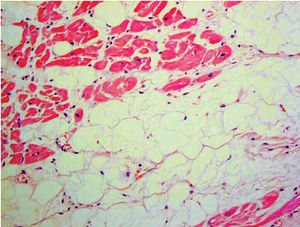

Biopsia endomiocárdica

El diagnóstico histológico es definitivo71 (fig. 4). Sin embargo, la utilidad de la biopsia endomiocárdica es muy controvertida debido al carácter segmentario de la enfermedad, la escasa afección del septo (lugar habitual para la obtención de la muestra), una alta tasa de complicaciones (taponamiento y perforación) en relación con el adelgazamiento de la pared miocárdica y la mayor dificultad técnica (frecuentemente se obtienen muestras de localizaciones no habituales)7.

Fig. 4. Muestra anatomopatológica: infiltración fibroadiposa del ventrículo derecho.